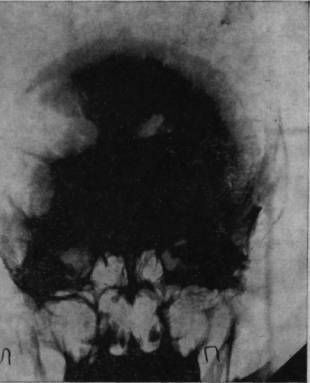

Рис. 1а. Рентгеновский снимок черепа больного Засецкого после введения воздуха в желудочки мозга (пнеймоэнцефалограмма). На нем можно видеть резко расширенный левый боковой желудочек и скопление воздуха в подоболочечных пространствах мозга теменно-затылочной области левого полушария

Осколок внедрился в вещество задних, теменно-затылочных отделов мозга и разрушил мозговую ткань этой области.

Ранение осложнилось воспалительным процессом; он не распространенный, местный, ограничен лишь областями мозга, примыкающими к непосредственному месту ранения, но теменно-затылочные отделы левого полушария, отделы, так тесно связанные с анализом пространственного мира, необратимо повреждены, и уже начинается процесс образования рубцов, который неизбежно повлечет за собою частичную атрофию расположенных вблизи ранения участков мозгового вещества.

Рис. 1б. Черное пятно в правом полушарии - осколок, расположенный под кожей от поверхностного шрапнельного ранения, полученного им за год до основного ранения

И через десять лет после ранения - еще одна выписка из истории болезни, на этот раз сделанная на основе рентгенограммы.

В спинномозговой канал введен воздух. Он поднялся вверх, заполнил контуры желудочков мозга и те пустоты, которые образовались в результате сморщивания вещества отделов мозга, непосредственно примыкающих к месту ранения. "Процесс рубцевания вызвал атрофические изменения в левом боковом желудочке. Стенки его подтянуты к поверхности мозга, подоболочечные пространства резко расширены. Значительный местный атрофический процесс".

Ранение вызвало местную атрофию мозгового вещества левой теменно-затылочной области.